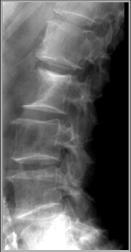

Aortic aneurysm